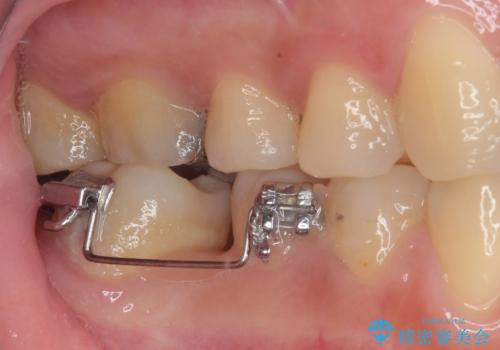

矯正装置を長いこと付けていたことで、歯が大きく捻転してしまい、舌に当たる感覚を気にしていらっしゃいましたが、補綴治療により捻転とともに解消することができました。

上顎の最後臼歯と咬み合わせるために前後径が大きくなっており、歯肉周りに汚れが溜まりやすくなるため、日々の清掃と定期的なクリーニングが必要となります。